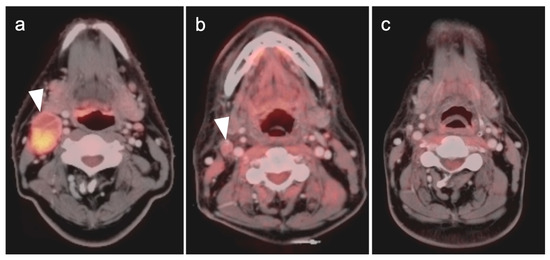

2.3. Nasopharyngeal Carcinoma

2.4. Sinonasal Tumors